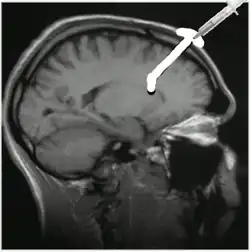

Ommaya rezervoár je druh intraventrikulárního (nitrokomorového) katétru, který se používá jak pro přímou a opakovanou intratekální aplikaci léků (např. chemoterapie) do mozkomíšního moku, tak pro odsávání mozkomíšního moku. Zařízení tak pacienta šetří opakovaných lumbálních punkcí.[1] Skládá se z katétru, který vede z laterální mozkové komory, respektive komorového systému mozku, do rezervoáru, který je implantován do podkoží hlavy.[2] Samotná aplikace ommaya rezervoáru je prováděna chirurgicky.[3]